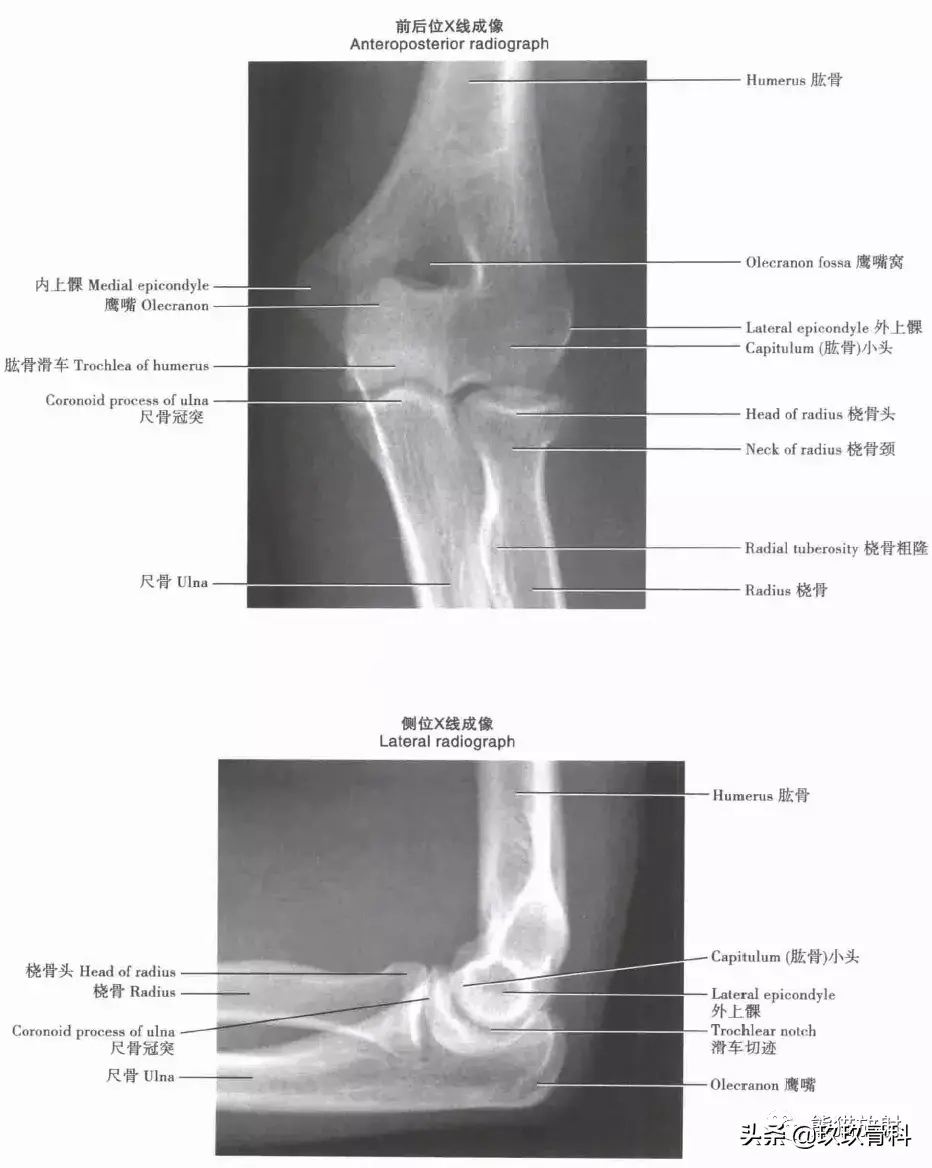

肘关节:X线成像